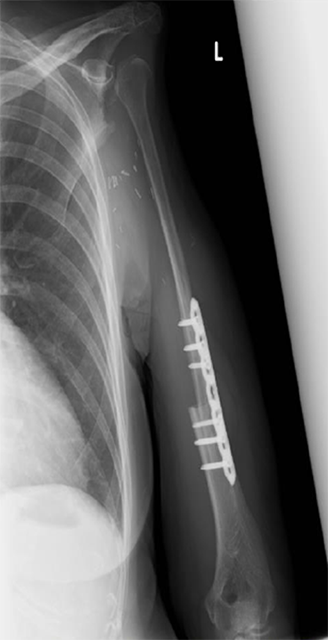

下腿にある腓骨と呼ばれる長管骨を採取し、移植します。骨と同時に皮膚も移植することができるため、骨欠損と軟部組織欠損を同時に治療することが可能です。また、血流のある骨移植であるため感染に対しても強く、感染性偽関節症例にも適応されます。

上腕骨腫瘍に対し、広範切除術と腓骨移植術を行った。